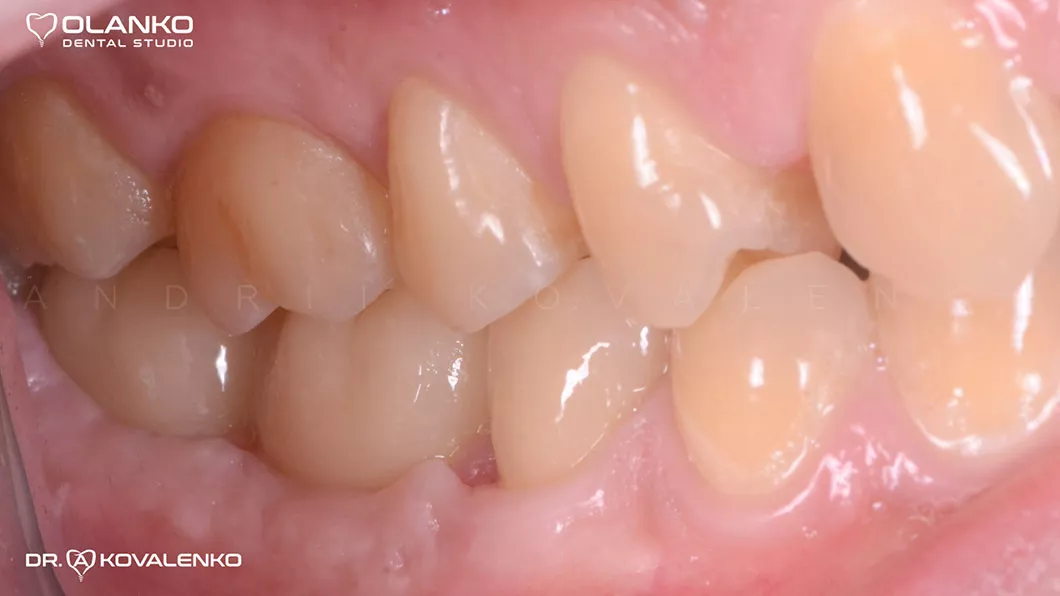

Пациент обратился с жалобами на боль и дискомфорт при жевании на нижней челюсти справа.

Лечение: удаление 2-х не подлежащих лечению зубов. Установка двух  имплантатов, с последующей установкой цельнокерамических коронок на индивидуальных абатментах.

Ситуация до

Вид через 4 месяца после удаления